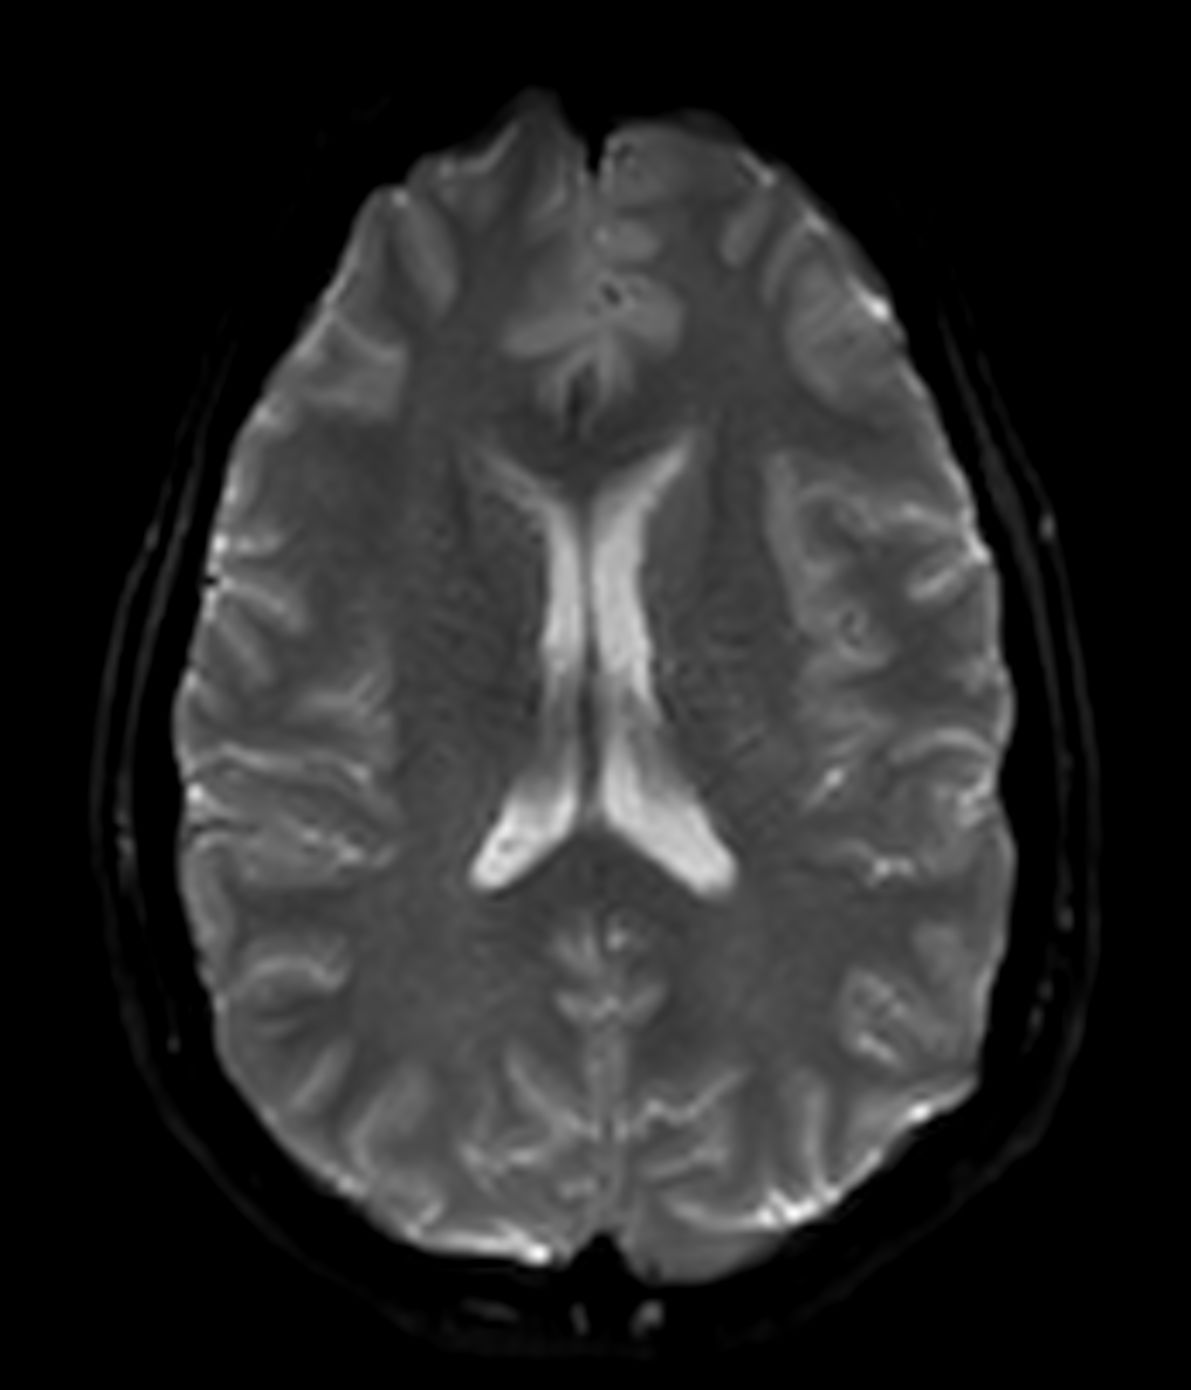

Alzheimer’s Disease Anti-Amyloid Immunotherapies (ARIA) 3.0T

Amyloid clearing medication, such as Aduhelm (Aducanumab) and Leqembi (Lecanemab) have been cleared by the FDA in 2022/2023, to slow down cognitive decline in early-stage Alzheimer’s disease. ASNR-recommendations for AD therapeutic imaging were published in 2022 for eligibility assessment as well as for monitoring for amyloid-related imaging abnormalities. This ExamCard includes ASNR-recommended consensus protocols for imaging of Alzheimer’s Disease Anti-Amyloid Immunotherapies (ARIA). (Cogswell et al., AJNR 2022,43(9)E19-E35;DOI: https://doi.org/10.3174/ajnr.A7586))